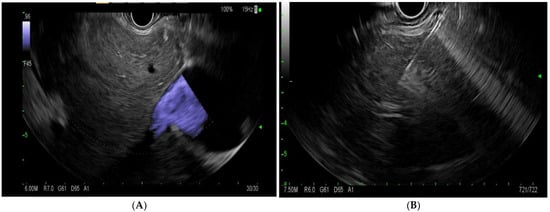

EUS-LB involves the use of an EUS linear echoendoscope and an endosonographic image with a doppler to guide the trajectory of the needle to obtain a liver biopsy (Figure 4). Prior to the procedure, doppler imaging is obtained to ensure vascular structures are present along the planned path of needle insertion [17]. This approach enables targeted sampling based on accurate endosonographic visualization to facilitate accurate sampling, diagnoses, and the subsequent management of various hepatic conditions. The first site to be identified is usually the left lobe of the liver, accessed from near the gastro-esophageal junction. Next, the right lobe of the liver is accessed from the duodenal bulb. The needle is passed at least 3 cm. In the event of wet heparinized suction, the stylet is primed with heparin and access is achieved. Suction is applied with a 20 cc vacuum syringe and completed with one pass utilizing up to five to-and-fro motions utilizing a fanning motion. Ideally, 2 such passes are made with a total of 10 actuations [17]. The specimen is promptly mounted on formalin. There have been various needle types and tissue acquisition techniques used in the assessment of hepatic parenchyma. Common needle types include 19 G flexible FNA needles (Expect; Boston Scientific, Marlborough, MA, USA); Franseen needles (Acquire; Boston Scientific, Marlborough, MA); reverse-bevel with tissue trap (ProCore; Cook Medical Inc, Winston-Salem, NC, USA); and 19 G Tru-Cut needles (Quick Core; Cook Medical Inc, Winston-Salem, NC). In the coming sections, we will review the most commonly used needle times for EUS-guided liver biopsy.

Figure 4.

(A)—endoscopic ultrasound image of the liver with doppler. (B)—endoscopic-ultrasound-guided liver biopsy using a 19 G needle.